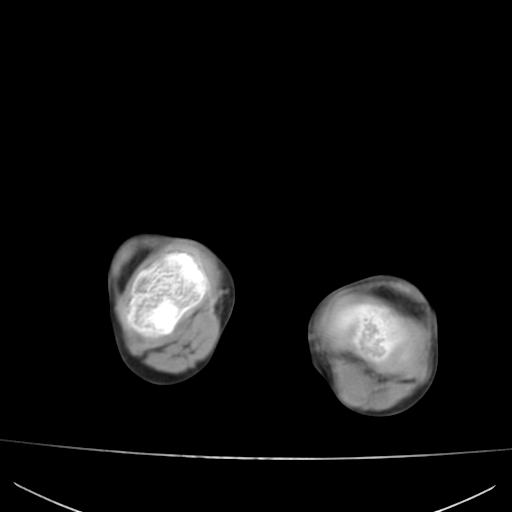

标题: PED0940:M12Y,左股骨下端酸痛畸形 [打印本页]

标题: PED0940:M12Y,左股骨下端酸痛畸形

12岁男孩,左膝关节肿痛8年,近月明显

内生骨软骨瘤?

血友性关节病?